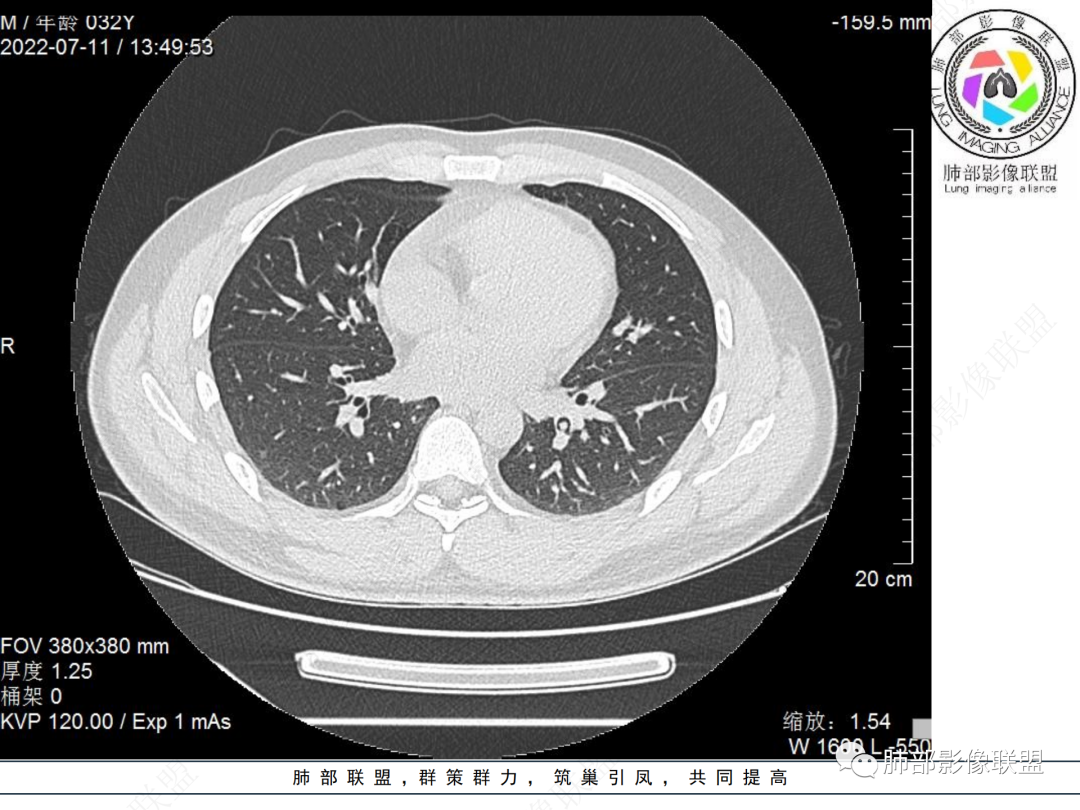

左肺下叶后基底段开口处结节,边缘光滑清楚,没有增强扫描,年轻男性患者痰血三天,考虑1.良性病变:腺瘤、错构瘤、平滑肌瘤

2.恶性:类癌、粘液表皮样癌。

左肺下叶外后基底段气管内见结节状影,边缘部分清晰。考虑错构瘤,待排恶性病变。

左肺下叶气管内外占位病变,咯血病史,考虑类癌,粘表待排。

青年男性,左肺下叶后基底段支气管开口软组织结节,边缘光整,气管镜提示质软,易出血,考虑类癌

左肺下叶后基底段开口处结节,边缘光滑清楚,年轻患者考虑鳞癌或腺样囊腺癌

左肺下叶气道腔内占位,远端无花花草草,疾病谱:鳞,类癌,粘表,腺样囊腺癌,小,无增强,不好判断,临床咯血,选类癌。

大支气管腔内结节,考虑类癌

左肺下叶后基底段开口处结节影,边缘光滑,患者年龄较小,首选类癌

男性,咳血左肺下叶支气管腔内结节影,没有阻塞性炎症,考虑类癌,鳞癌

年轻男性,支气管内结节,首先类癌

左肺下叶后基底段开口处腔内见壁结节,花生米样,宽基底,补充增强及矢状位重建,确定我无向壁外突破浸润生长,另见强化的特点,临床触之易出血,类Ca可能性大。

年轻男性,支气管腔内占位,边缘尚平整,年轻人,首先类癌,鉴别错构

年轻男性,咳血,左肺下叶后基底段支气管腔内结节,边缘光滑,首先考虑青年三件套,类癌大于粘液表皮样癌,支气管镜质软,触之易出血,鉴别血管瘤,平滑肌瘤

左肺下叶后基底段开口部结节,密度较均匀一致,边缘较光整,目测密度偏低,支气管镜示:质软、触之易出血,考虑恶性,类癌。

支气管腔内结节,有蒂与支气管壁连接,考虑良性病变可能性大,支气管错构瘤 血管瘤一类的

左肺下叶后基底段支气管腔内结节,有蒂,容易出血,先考虑良性病变,肉芽组织型血管瘤,与类癌鉴别。

青年男性,左肺下叶后基底段支气管开口软组织结节,边缘光整,气管镜提示质软,易出血,考虑恶性类癌

左肺下叶后基底段开口处结节影,边缘光整,年轻患者,伴咯血,考虑鳞癌,类癌不能排除